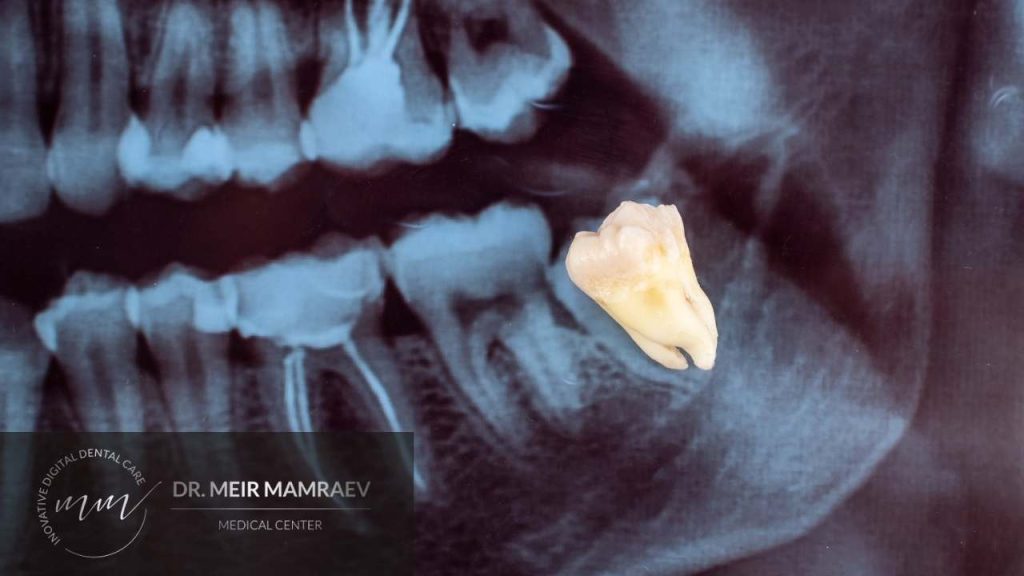

עקירת שן בינה כלואה נעשית בדרך כלל בהרדמה מקומית. במקרים מיוחדים כגון מטופל הסובל מחרדה דנטלית ניכרת או כאשר שוקלים לעקור כמה שיניים בו זמנית, ניתן לבצע את הטיפול בהרדמה כללית. לצורך העקירה רופא השיניים מבצע חתך בחניכיים כדי לחשוף את השן. אם השן תקועה היטב הרופא יפצל את השן או יסיר מעט עצם סמוכה באופן שמקל על "שליפת" השן החוצה. בשלב הבא הרופא סוגר את המקום בתפרים.

פעולת העקירה בדרך כלל מסתיימת די מהר. כאשר השן לא כלואה בחוזקה או שאיננה עקומה במיוחד, העקירה יכולה להסתיים בתוך דקות ספורות. במקרים שבהם השן מאוד עקומה או שיש לה שורשים מפותלים וצריך לפצל את השן לפני הוצאתה, הטיפול עשוי לארוך כחצי שעה עד שעה.